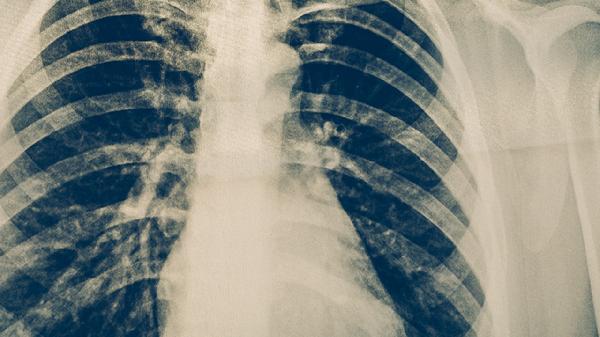

中医治疗肺结核的方法主要有中药汤剂、针灸疗法、艾灸疗法、食疗调理、气功疗法等。肺结核在中医称为肺痨,多因正气不足、痨虫侵袭所致,需结合辨证施治原则干预。